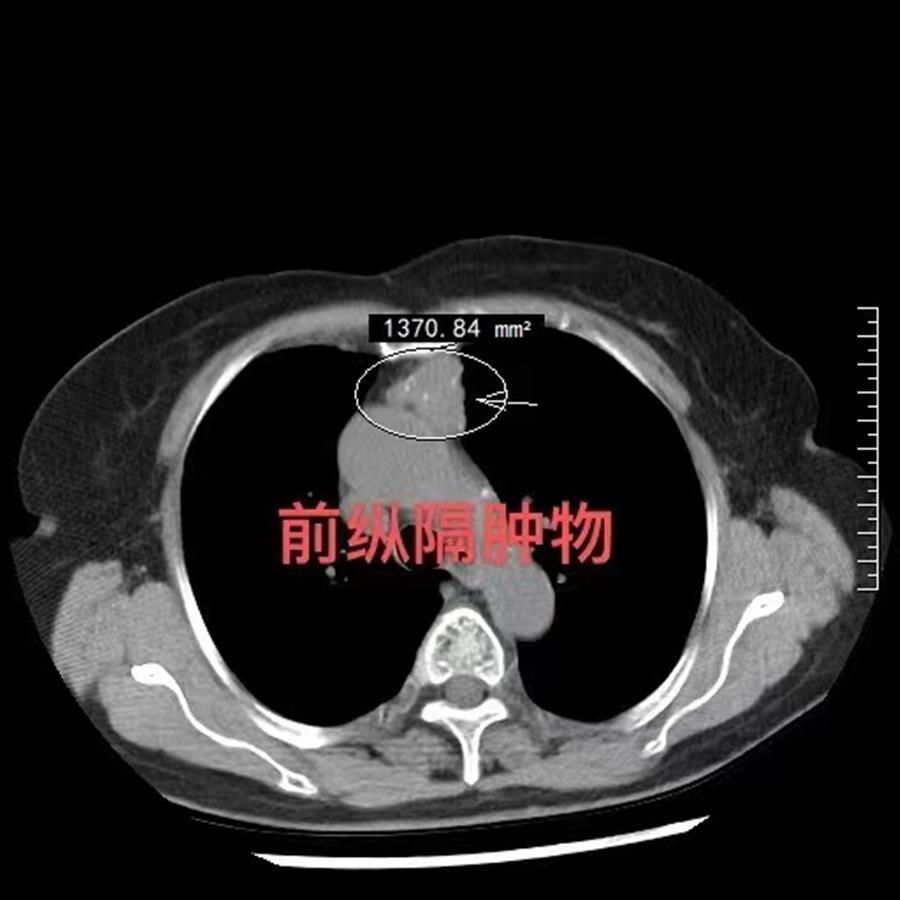

77岁易奶奶来自湖北荆州。去年11月,因胸闷、呼吸不畅,通过CT检查发现前纵隔占位,家人带着她慕名找到武汉大学人民医院胸外科行政副主任、主任医师林慧庆教授寻求帮助。

经过常规系列检查后,初步判定为纵隔肿瘤,但在完善术前常规检查中,林慧庆教授意外发现,一颗“不定时炸弹”隐藏在右侧颈内动脉远端分叉处,瘤体截面约7x5.8毫米。进一步完善颅脑MRI提示:大脑中动脉走形异常,动脉瘤可能性大。